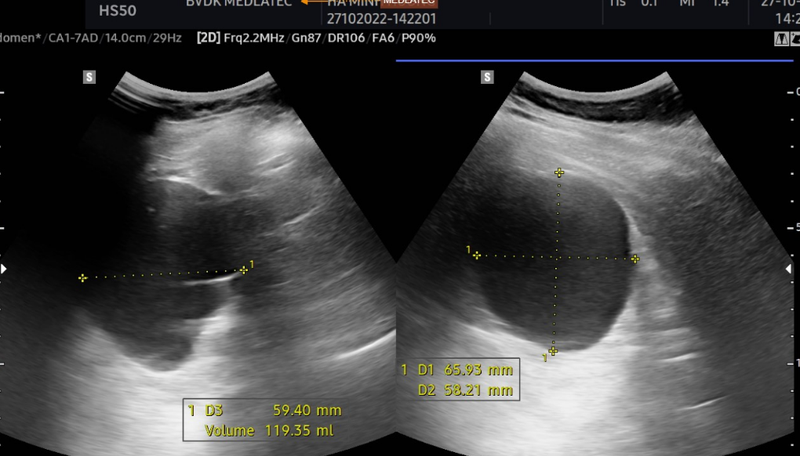

Có nhiều phương pháp để chẩn đoán nang thận gồm: CT-scan, siêu âm, thực hiện các xét nghiệm bổ sung như tổng phân tích nước tiểu, xét nghiệm chức năng thận, xét nghiệm công thức máu,... Trong đó, siêu âm ổ bụng và siêu âm hệ tiết niệu là cần thiết được áp dụng rộng rãi hiện nay để phát hiện vị trí và kích thước nang thận.

Siêu âm thận là phương pháp chẩn đoán hình ảnh dùng dòng sóng siêu âm có tần số lớn để tạo ra những hình ảnh về kích thước, cấu trúc của thận, từ đó có thể tìm được các dấu hiệu bệnh lý của thận. Việc chẩn đoán sớm các bệnh lý của thận như nang thận chẳng hạn sẽ hỗ trợ bác sĩ trong việc điều trị phù hợp, giúp hiệu quả chữa bệnh nâng cao. Siêu âm là phương pháp không xâm lấn nên an toàn cho người bệnh.

Chẩn đoán nang thận chủ yếu bằng cách siêu âm hệ tiết niệu, giúp bác sĩ đánh giá được kích thước, số lượng nang và thành của nang thận.